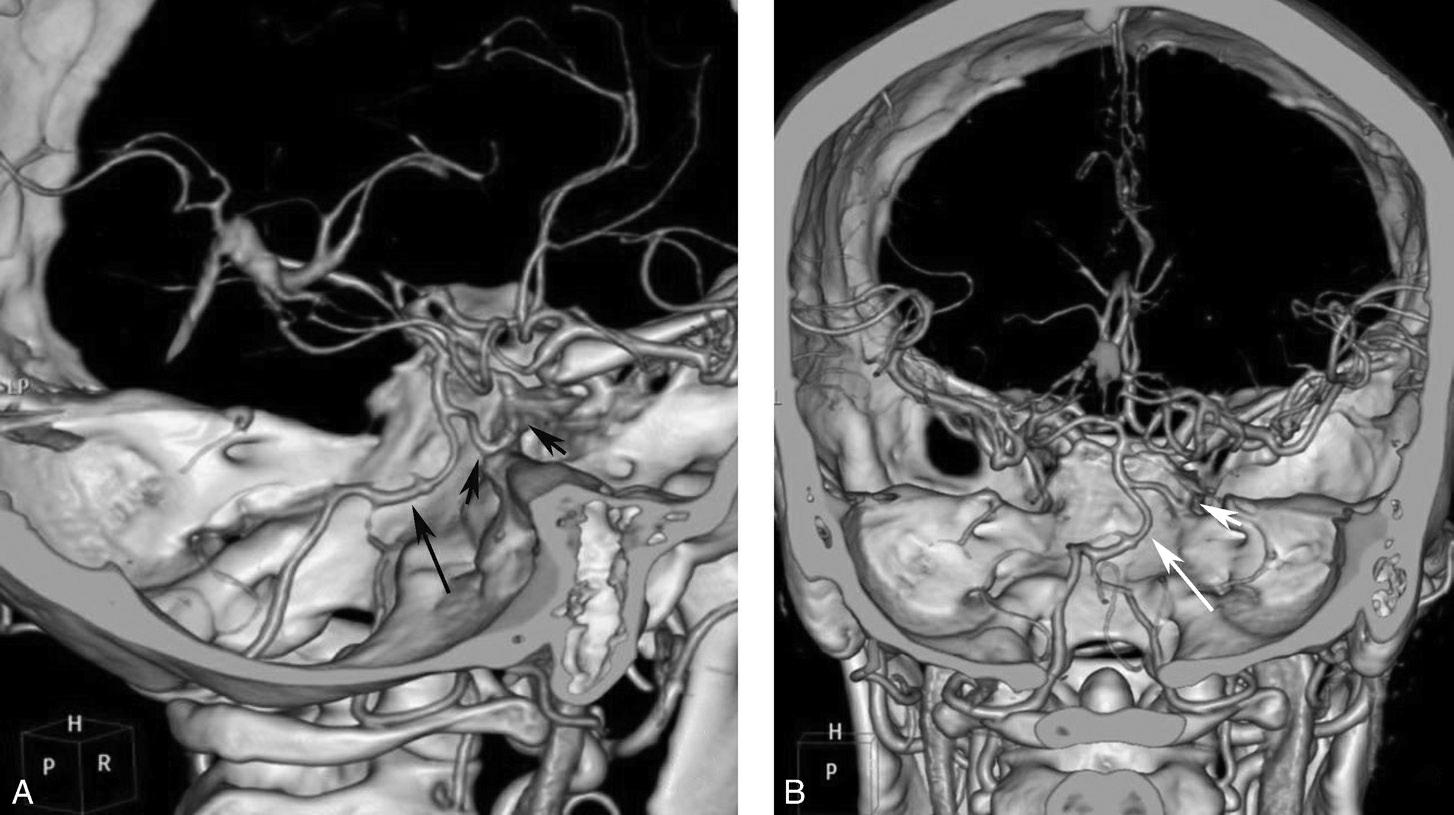

图1-2-111 前交通动脉瘤

CTA示前交通囊状动脉瘤,瘤颈较宽

图1-2-112 大脑后动脉瘤

双侧大脑后动脉各见一宽颈、囊状动脉瘤(箭、箭头)

图1-2-113 基底动脉瘤

基底动脉尖一类圆形动脉瘤(箭)

图1-2-114 颈内动脉瘤

颅脑CTA示右侧颈内动脉C 7 段囊状突起(箭),表面光滑